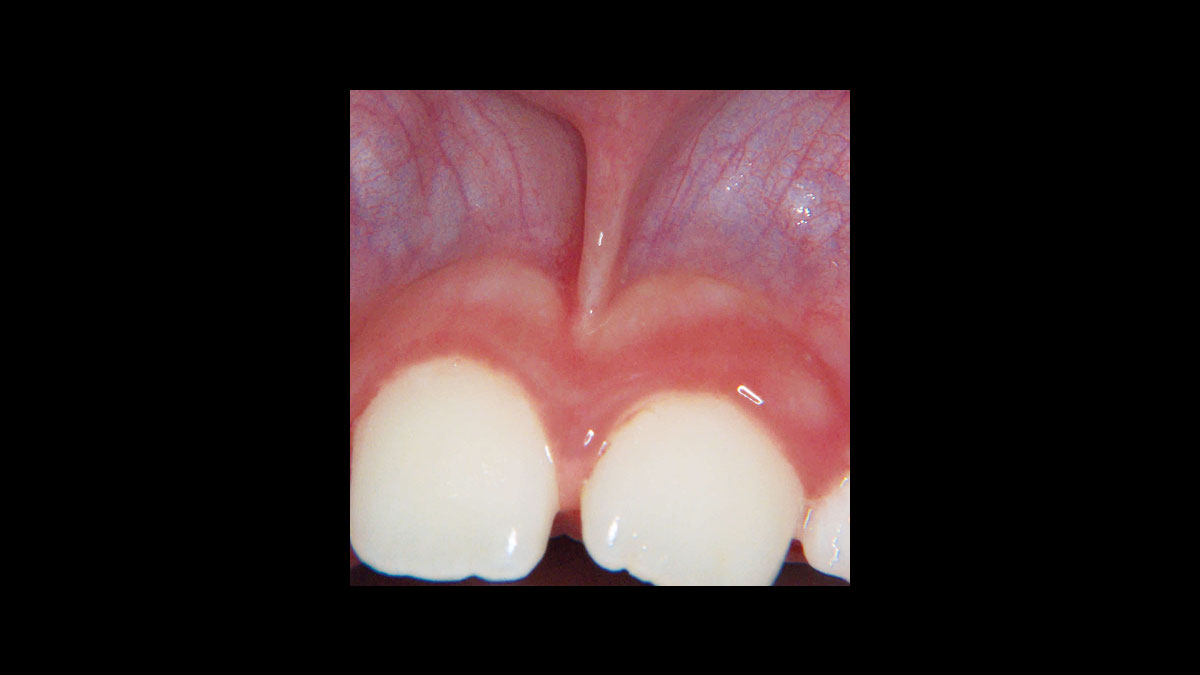

Diode Laser Implant Uncovery . This study was designed to assess if dental implant uncovering is possible with a diode laser without anesthesia versus. The laser is ideal for implant uncovery and tissue modification around implants because there is little to no bleeding and. This article presents two cases in which four dental implants were uncovered using a soft tissue laser. One can either use a tissue punch, a diode laser or a. This article presents two cases in which four dental implants were uncovered using a soft tissue laser. This article presents two cases in which four dental implants were uncovered using a soft tissue laser. Diode lasers, such as the picasso lite+ (amd lasers, west jordan, utah, www.amdlasers.com) (fig. 1), provide adequate power to modify soft tissue in and around the dental implant for uncovery or alteration of the gingival margin to improve the esthetics. There are multiple ways to uncover an implant during second stage surgery.

Diode Laser Implant Uncovery The laser is ideal for implant uncovery and tissue modification around implants because there is little to no bleeding and. One can either use a tissue punch, a diode laser or a. Diode lasers, such as the picasso lite+ (amd lasers, west jordan, utah, www.amdlasers.com) (fig. This article presents two cases in which four dental implants were uncovered using a soft tissue laser. The laser is ideal for implant uncovery and tissue modification around implants because there is little to no bleeding and. This article presents two cases in which four dental implants were uncovered using a soft tissue laser. There are multiple ways to uncover an implant during second stage surgery. 1), provide adequate power to modify soft tissue in and around the dental implant for uncovery or alteration of the gingival margin to improve the esthetics. This study was designed to assess if dental implant uncovering is possible with a diode laser without anesthesia versus. This article presents two cases in which four dental implants were uncovered using a soft tissue laser.